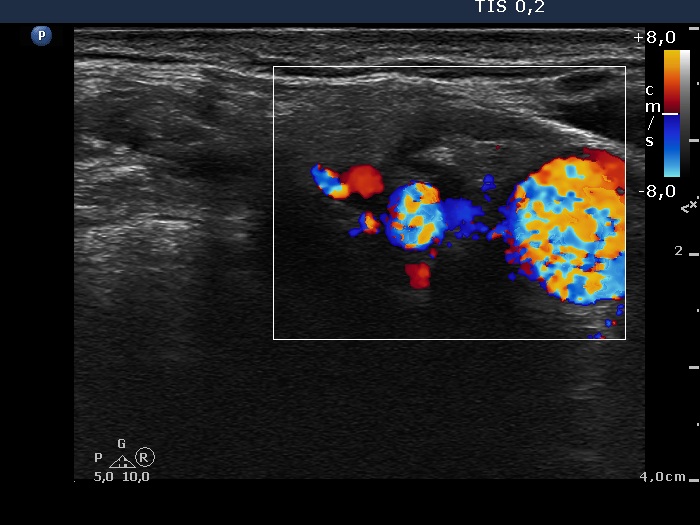

Right lobe, longitudinal scan

Above the left lobe, transverse scan, color Doppler mode. The node is avascular.